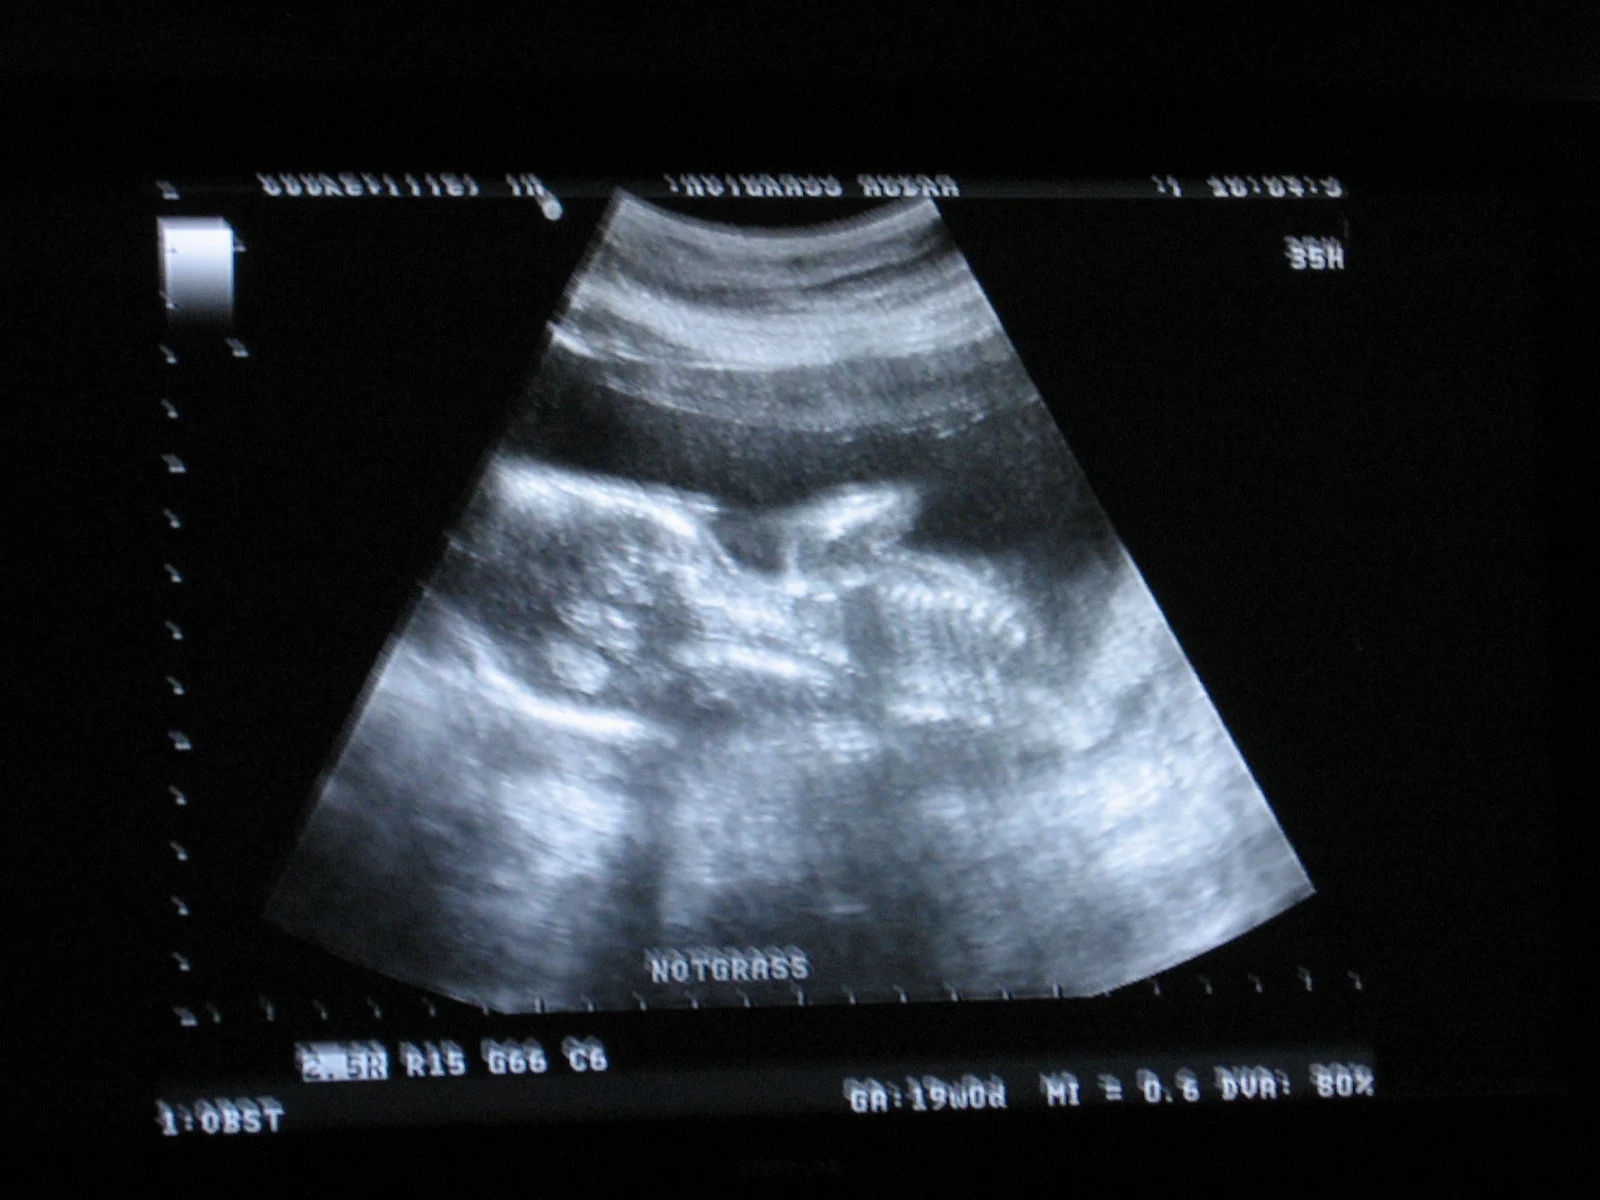

In November of 2011, God blessed us with another child, our fourth in three years. OB appointments were not quite as hard, but we were always relieved when we heard the heartbeat and got a good report.

Another Beautiful Peanut

During the ultrasound to find the child’s gender, the technician noticed that the umbilical cord only had two vessels instead of three. A two-vessel cord is often present when other abnormalities are found, but she did not find any other abnormalities. Our OB sent us to a high-risk specialist for more detailed observation. Henry did not cooperate on the first visit, so we had to go back for a second check up. The high-risk folks did not find any other cause for concern, so we just had to wait it out.